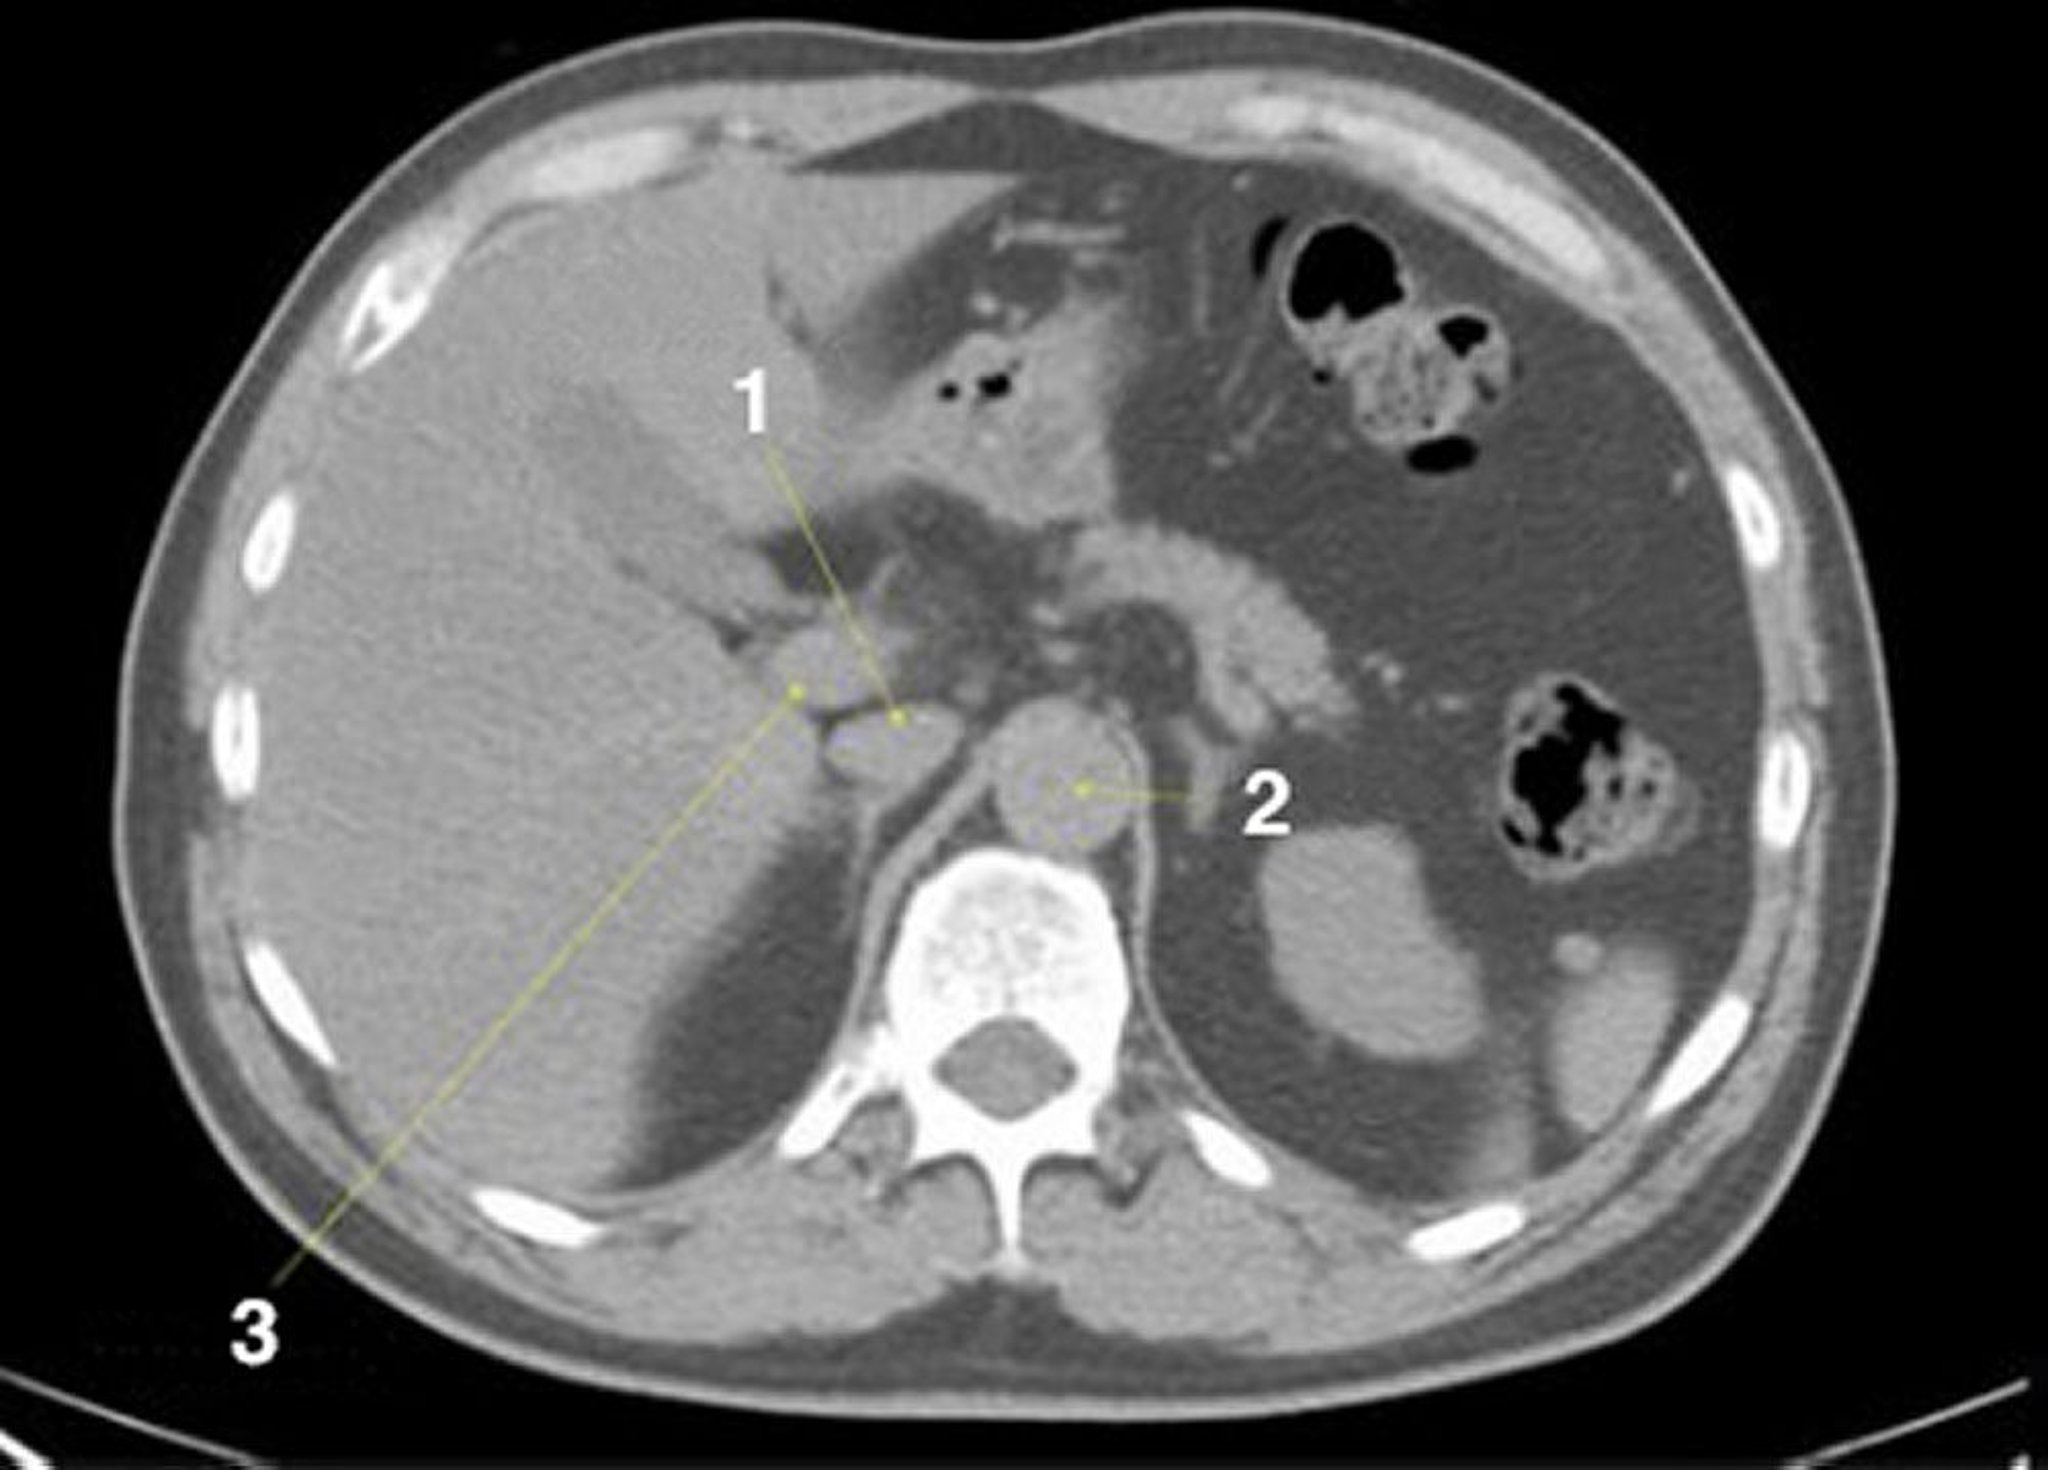

TDM sans contraste de l'abdomen et du bassin montrant une anatomie normale (diapositive 6)

1 = veine cave inférieure; 2 = aorte; 3 = veine porte.